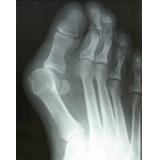

කකුලේ මහපට ඇගිල්ල ඇදවීම

එහිදී මහපට ඇගිල්ල කකුලේ දෙවෙනි ඇගිල්ල වෙත තල්ලු විම සිදුවේ

මහපට ඇගිල්ලේ ඇතුලු දාරයේ සම ඝණ වීම

මහපට ඇගිල්ල සවිවන හන්දියේ ඇතිවන වේදනාව

මහපට ඇගිල්ල අනෙක් ඇගිලි දෙසට නැවීම